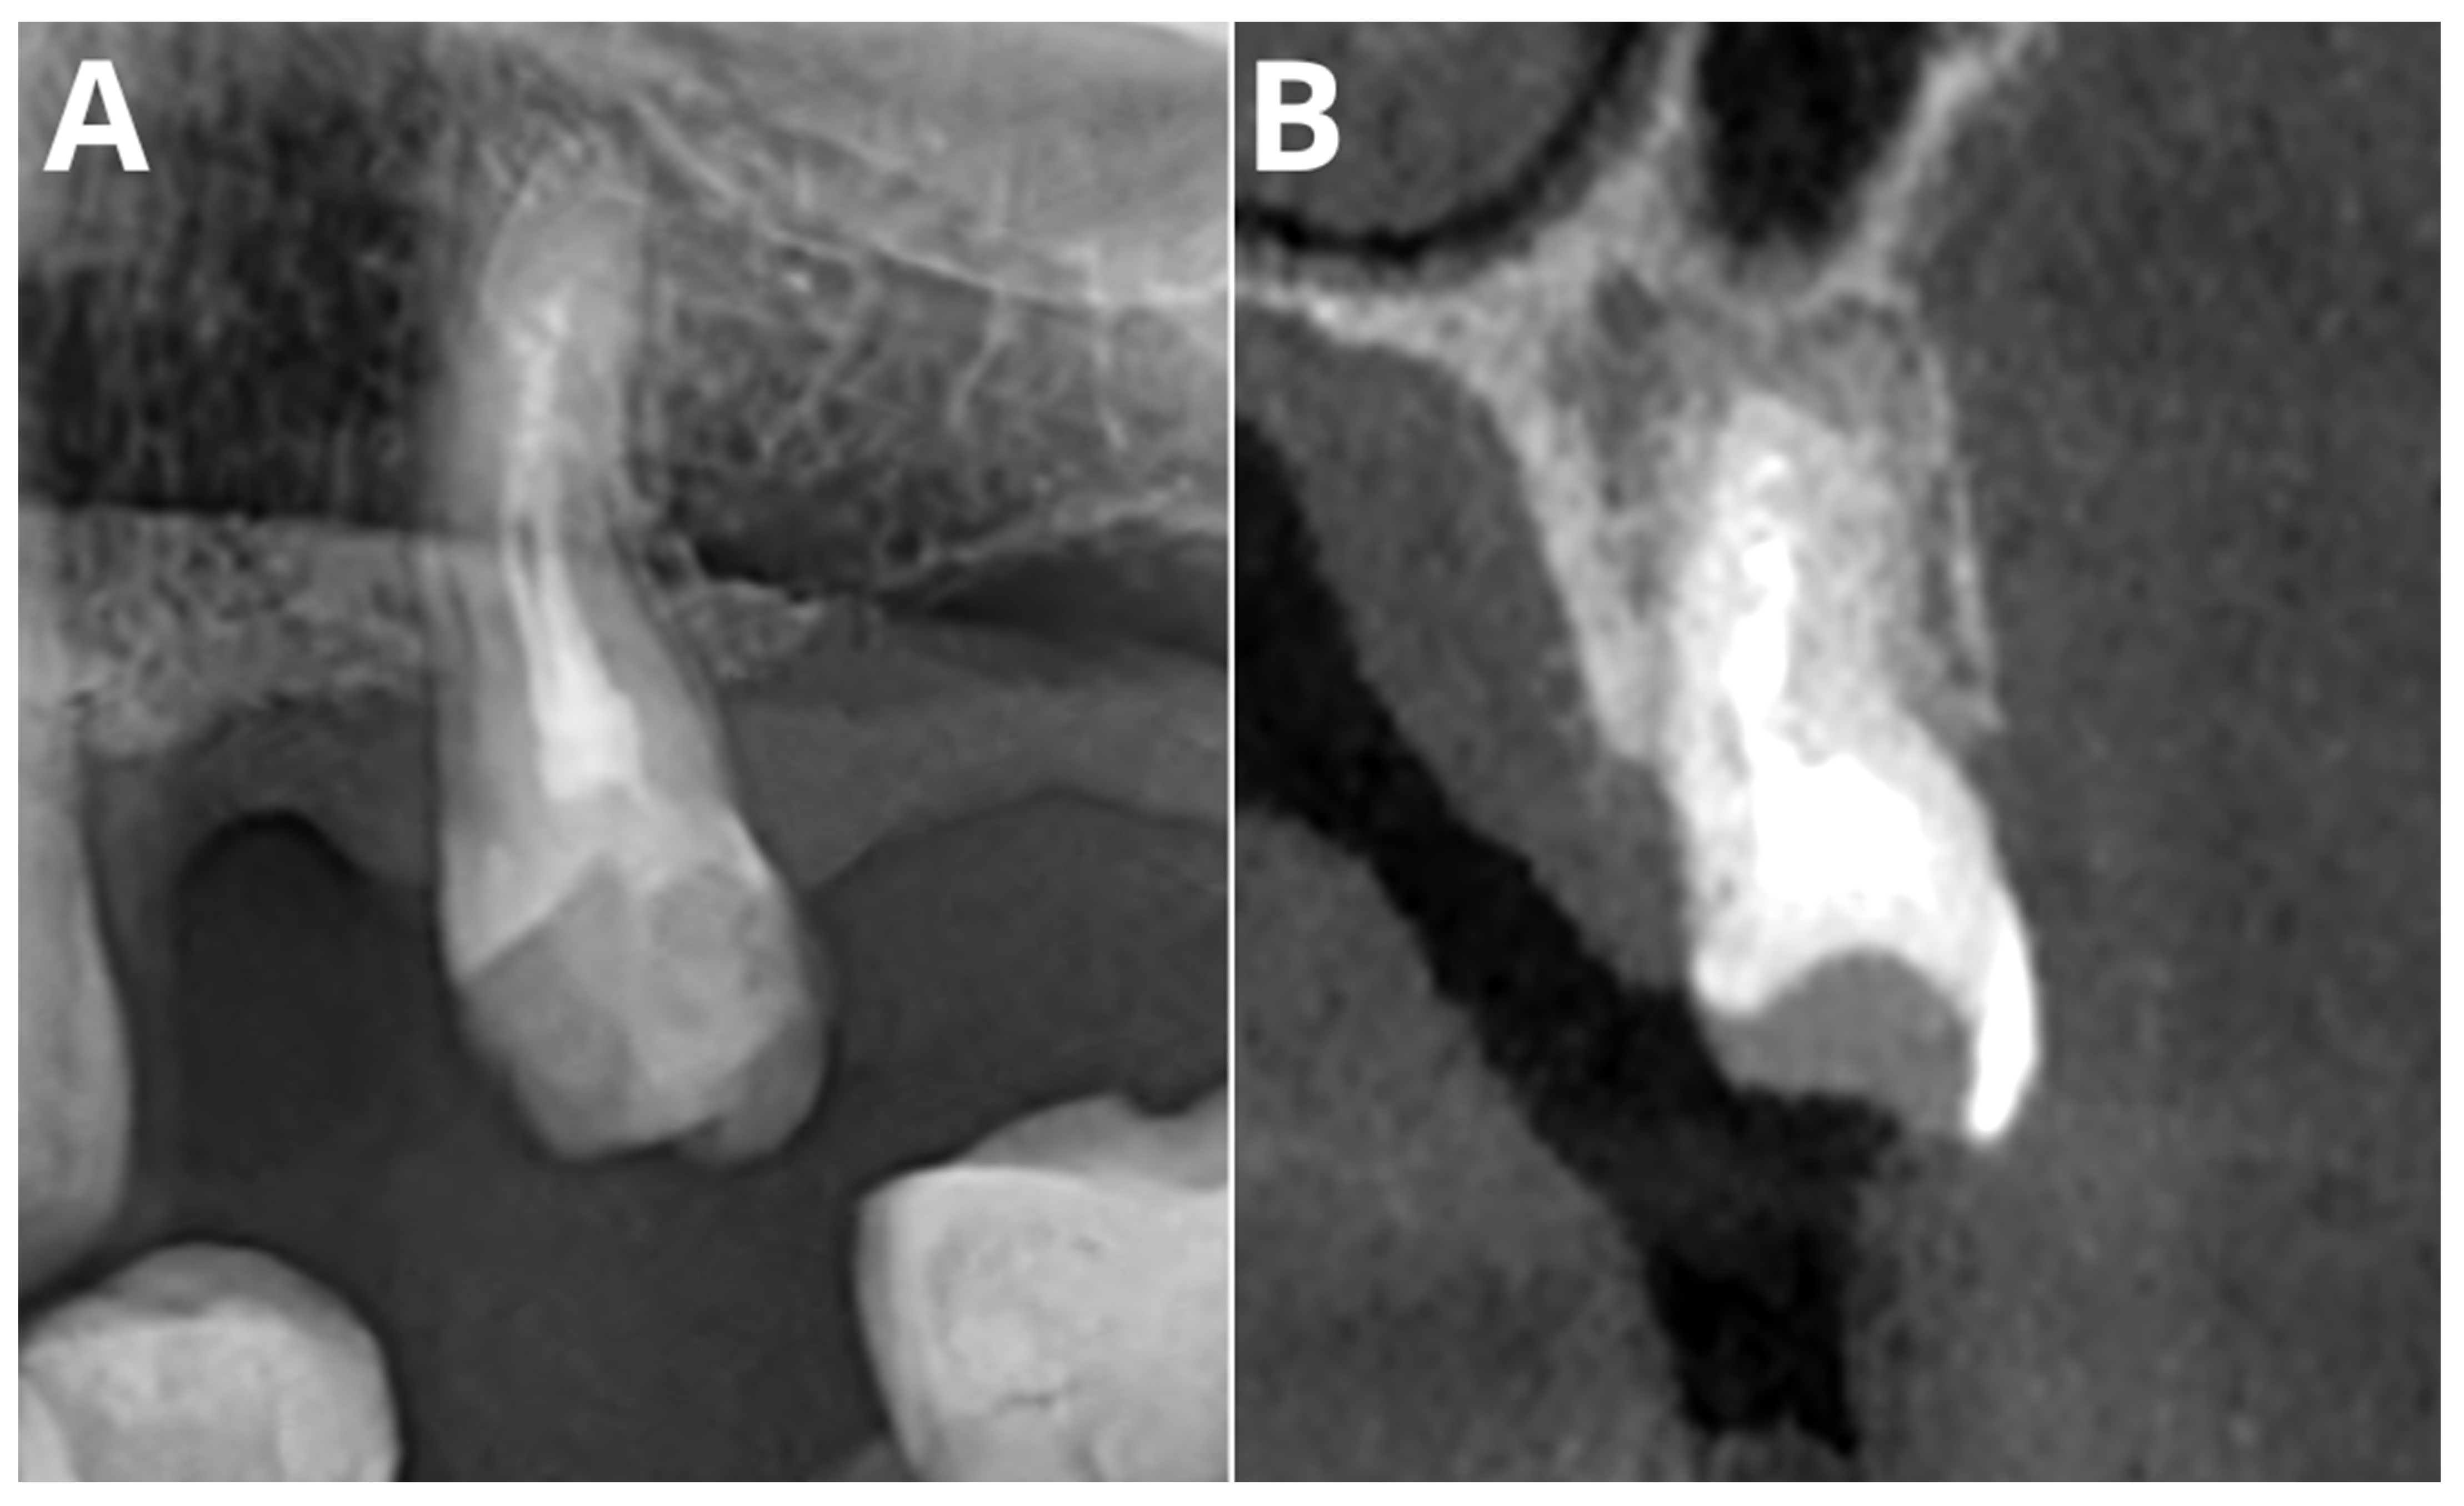

Periapical Lesions in Panoramic Radiography and CBCT Imaging—Assessment of AI’s Diagnostic Accuracy

2. Materials and Methods

2.2. Image Acquisition and Post-Processing